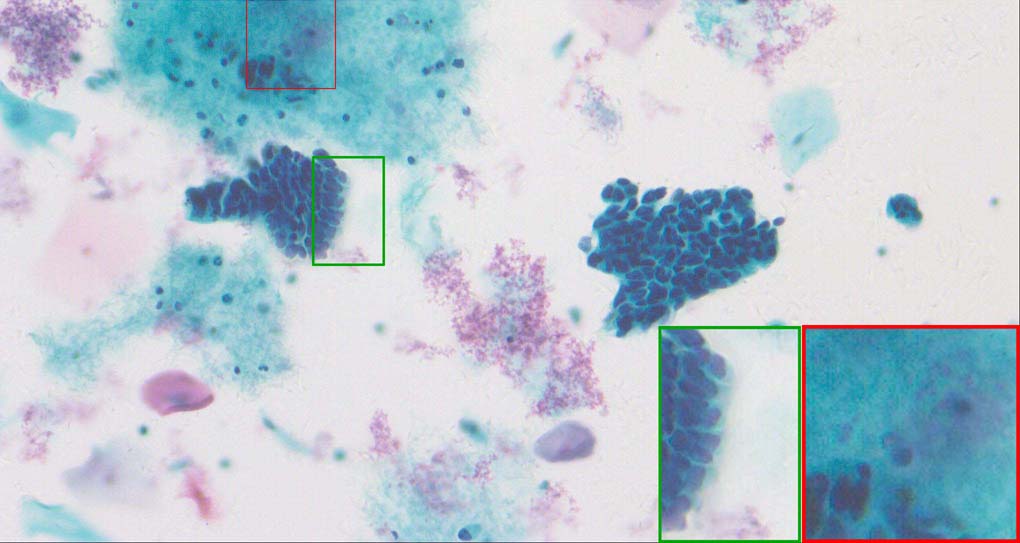

To demonstrate the effectiveness and efficiency of the proposed image fusion method , we conduct a set of comparative experiments on three image datasets. The first is composed by 8 pairs of multi-modal medical images and the second one contains 15 pairs of multi-focus gray or color natural images. These two datasets are often used in many related papers and some examples are shown in Figure 3(a) and Figure 3(b). The third one is a new multi-focus cervical cell image dataset collected by ourselves, which consists of 15 groups of color images and each group contains a series of multi-focus cervix cell images with size of or , etc. Some source examples are shown in Figure 3(c). Our source code implemented in C++ along with the new multi-focus cervical cell image dataset is available online.

Figure 9, Figure 10 and Figure 11 show the comparative fused results of the multi-focus cell images shown in Figure 3(c). For clarity, we also present a closeup view in the right-bottom of each sub-picture in Figure 9 and Figure 10. As shown in the close-up views of Figure 9, the fused images based on DSIFT, IM, MWGF and BF methods are extremely blurred in the boundary and fail to keep the details of cell nucleus. Furthermore, the DTCWT and NSCT based methods produce halo artifacts in the fused images, while GFF and CNN based methods fail to preserve the small cell nucleus. LP-SR based method nearly works fine which keeps the most of the details of the small size cells, but the integrity of the clustered large size cells is damaged. Fortunately, in our proposed method, the integrity of the clustered large size cells is preserved and most of the isolated small size cells are maintained from the original images, which demonstrates the best visual quality.

Similarly, as shown in the close-up views of Figure 10, the fused images from DSIFT, IM, MWGF and BF are blurred and lose some nucleus details, while the results from DTCWT, GFF, CNN and NSCT produce halo artifacts. LP-SR based method can keep details well but also produces halo artifacts and other noise. Our method can preserve the focused areas of different source images well without introducing any artifacts. For the example illustrated in Figure 11, the fused images generated by DSIFT, DTCWT, IM and NSCT all fail to preserve the focused areas of different source images and result in extremely blurred images. The GFF, CNN, MWGF and BF based method introduces a lot of color distortion of the nucleus regions and the obvious halo artifact. The result of LP-SR based method is close to the one of our method but introduces some odd color distortion. Again, our method produces fused image which can preserve the focused areas of different source images well without introducing any artifacts.